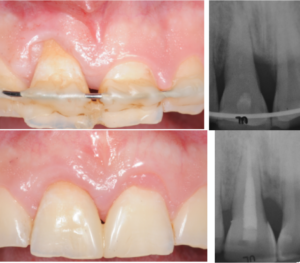

Traditionnellement, les résultats d’une thérapeutique de régénération parodontale étaient évalués par le comblement du défaut osseux d’un point de vue radiographique et par le gain d’attache clinique.

Aujourd’hui, au niveau des zones esthétiques, ces aspects ne suffisent plus. L’amélioration de l’esthétique des tissus mous associée à la régénération parodontale, est primordiale.

Une nouvelle procédure, combinant une technique de préservation papillaire avec greffe de tissu conjonctif et lambeau déplacé coronairement, sera présentée. La greffe de tissu conjonctif joue le rôle de paroi vestibulaire du défaut intra-osseux, traité par apport d’amélogénines, augmentant ainsi la stabilité du caillot

sanguin pour favoriser la régénération parodontale et améliorer le résultat esthétique.